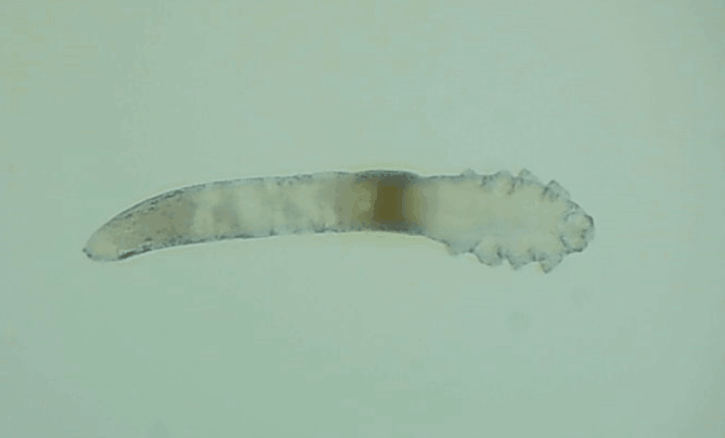

是的, 眼睛也會(huì)有蟲子,那就是蠕形螨。眼睛發(fā)紅、干癢、疲勞、睫毛脫落,這些都是因?yàn)樗?/div>

其實(shí)蠕形螨主要活動(dòng)在毛囊和皮脂腺中,以皮膚碎屑和腺體分泌物作為食物來(lái)源,而睫毛根部的瞼板腺是排泄油脂的重要部位,因此眼睫毛和瞼板腺也是螨蟲的主要活動(dòng)場(chǎng)所。

一般來(lái)說(shuō),15天內(nèi),一只蠕形螨會(huì)在你眼睛里產(chǎn)下50只蟲卵。如果不及時(shí)除螨,它們會(huì)迅速繁殖,從而導(dǎo)致睫毛脫落、亂生、眼睛紅癢,甚至引發(fā)眼部炎癥。如果影響到角膜,就會(huì)造成視力下降甚至失明。

在廈門眼科中心檢查后發(fā)現(xiàn),在她的眼睛上竟然有大量的螨蟲,僅是檢查用的2、3根睫毛上就有8只,除螨蟲外,她的眼睛還出現(xiàn)了瞼緣炎以及干眼癥。